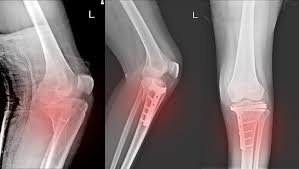

Knee fracture surgery in Pune becomes essential when an injury disrupts the knee’s ability to bear weight, bend smoothly, or remain stable during movement. Because the knee absorbs significant stress during daily activities, fractures in this region often affect more than just bone continuity. Consequently, untreated or improperly healed fractures may lead to stiffness, deformity, or early joint degeneration. Patients therefore require timely, well-planned surgical care that focuses on both healing and long-term function.

Fractures involving the tibial plateau often affect joint smoothness and weight distribution. Similarly, displaced patella fractures interfere with knee extension and muscle coordination. Distal femur fractures near the knee joint frequently result from high-energy trauma and require precise reconstruction. Because swelling and pain may initially mask internal damage, delayed diagnosis often worsens outcomes. Early orthopedic evaluation ensures timely surgical planning and improved recovery potential.

Knee fracture surgery at Dr. Aniruddha’s Advance Ortho And Polyclinic begins with a detailed assessment of fracture geometry and joint involvement. Dr. Aniruddha Deshmukh carefully studies imaging, limb alignment, and functional demands before finalizing the surgical approach. This step ensures that fixation supports both healing and future knee movement.

During surgery, fixation methods are selected based on fracture mechanics rather than routine preference. Plates, screws, or stabilizing systems are used to restore alignment while preserving surrounding tissues. Because joint surface restoration directly affects long-term comfort, accurate reconstruction reduces the risk of stiffness and post-traumatic arthritis. Patients undergoing knee fracture surgery in Pune therefore benefit from improved joint stability and predictable recovery.